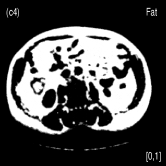

We also evaluated the proposed PWLS-TNV- method using clinical pelvis data. The patient’s pelvis data was acquired by Siemens SOMATOM Definition flash CT scanner using DECT imaging protocol. Table 4 lists acquisition parameters in the pelvis data scan. Fig. 5 shows the high- and low-energy CT images of the pelvis data. Fig.5 (b) shows selected basis materials, bone, iodine, muscle, fat and air, and their assosicated ROIs highlightened in white dashed line circles. We implemented the Direct Inversion method in mendonca2014a and used its results as the initialization for the PWLS-EP-LOOP xue2017statistical and the proposed PWLS-TNV- method. Fig. 6 shows the decomposed material images by the Direct Inversion, the PWLS-EP-LOOP and the PWLS-TNV- method. Table 5 summarizes the means and noise STDs of the decomposed material images by the above three methods. The volume fraction (VF) accuracies are , , and for the Direct Inversion method, the PWLS-EP-LOOP method and the proposed PWLS-TNV-, respectively. Compared with the Direct Inversion and PWLS-EP-LOOP method, the proposed method improves the VF accuracy by and respectively. The proposed PWLS-TNV- method decomposes basis material images more accurately, suppresses noise and decreases crosstalk, while retaining spatial resolution of the decomposed images compared to the other two methods.